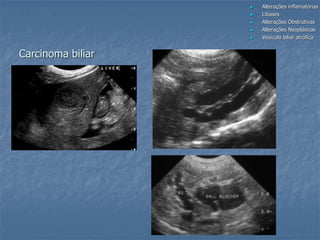

 Na vesícula biliar:

- benignas (pólipos, cistoadenomas)

- malignas (carcinomas)

 Nas vias biliares: aspecto variável não

distinto das neoplasias hepáticas

Carcinoma biliar

Fonte: Nyland, 2004

Carcinomatose